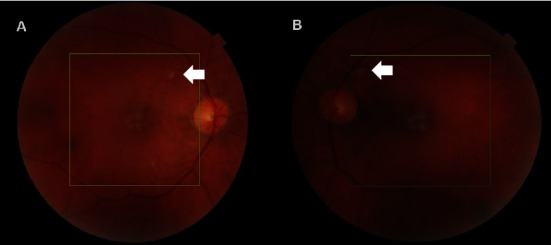

据我们所知,这是我们发现的首例Ⅱ型急性黄斑神经视网膜病变(AMN)病例,患者患有疟原虫性视网膜病变,同时伴有脑疟疾,在前往西非旅行时未采取必要的抗疟预防措施。患者在重症监护室解除镇静后,主诉双侧视力模糊。随后的检查发现双侧视网膜出血、棉絮状斑点和眼窝色素改变,表明患者患有疟原虫视网膜病变。黄斑光学相干断层扫描(OCT)显示,丛状外层和核外层(ONL)出现斑片状高反射变化,与 OCT 血管造影(OCT-A)显示的深层毛细血管丛流动空洞区域一致。本病例报告进一步揭示了疟原虫视网膜病变中神经感觉视网膜缺血的程度,并展示了一种新的成像生物标志物,可用于评估和量化该疾病造成的功能障碍。

To the best of our knowledge, we present the first case of type II acute macular neuroretinopathy (AMN) exhibiting in a patient suffering from malarial retinopathy concomitant with cerebral malaria acquired after travelling to West Africa without taking the necessary antimalarial prophylaxis. The patient complained of bilateral blurring of vision after being removed off sedation whilst at the intensive care unit. Subsequent examination revealed bilateral retinal haemorrhages, cotton-wool spots, and foveal pigmentary changes in keeping malarial retinopathy. Macular optical coherence tomography (OCT) revealed patchy hyperreflective changes at the level of the outer plexiform and outer nuclear layers (ONL) in keeping with the areas of deep capillary plexus flow void noted on OCT-angiography (OCT-A). This case report sheds more light on the extent of neurosensory retinal ischaemia in malarial retinopathy and showcases a new imaging biomarker which may be utilized in assessing and quantifying the functional deficit created by this disease.